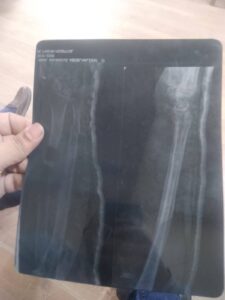

كما صرح ، وكيل الوزارة أن السيدة حضرت إلى قسم الطوارئ وهي تعاني من آلام شديدة، وإجراء الفحوصات الطبية

والأشعات اللازمة تبين إصابتها بكسر متفتت في الساعد الأيمن،

وعلى الفور تم اتخاذ القرار بالتدخل الجراحي العاجل نظرًا لدقة الحالة وطبيعة الكسر وعمر المريضة.

وحيث تم تثبيت الكسر باستخدام شريحة ومسامير طبية دقيقة، مما ساهم في استقرار الحالة الصحية للمريضة وبدء مرحلة التعافي.